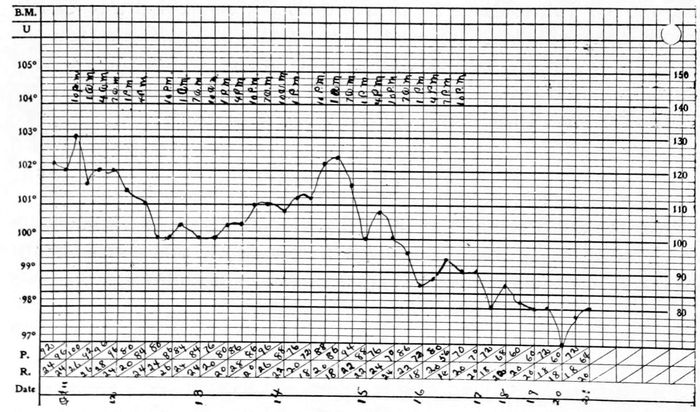

In all descriptions of the disease the duration is spoken of as “several days, more or less,” “a three-day fever,” or “a seven-day fever.” Because of the careful supervision under which the soldiers were kept while in the barracks an excellent opportunity was afforded to note the duration of uncomplicated cases. The shortest time observed was 1 day, and the longest 10 days. The average duration of temperature among 87 soldiers without inflammation of the lungs or other certain complications was 6⅓ days. Among the civilians the shortest time of pyrexia was a few hours only, while the longest in 73 male patients was 14 days, and in 84 female patients was 16 days. The average length of pyrexia in the males was 4⅝ days, and in the females was 5¼ days.